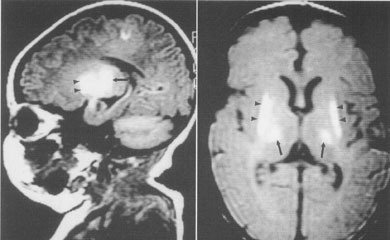

出血多在脐部和消化道,也可在鼻部成肾脏,严重的可发生颅内出血.

出血量一般不多,消化道出血最为常见,大便中有少许血,出血量多时,大便可呈柏油样或吐出血液,面色苍白,甚至休克。

新生儿颅内出血